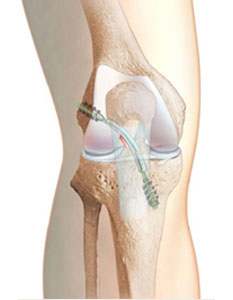

Once the graft tissue has been prepared and the torn ACL tissue has been removed, the surgeon is ready to place the ligament within the Knee. Small tunnels (7-10 mm) are drilled in the tibia and femur to allow the ligament to be pulled up into the Knee.

Accurate placement of these tunnels is critical to successful ACL Reconstruction Surgery. After the ACL graft is in position, fixation devices (screws, washers, buttons, etc.) get used to keep it there until it can heal into its place.

- After harvesting the tissue, a hole is drilled from the front of tibia diagonally into the Knee and ends up where the ACL attaches to the top of the shin. Next, the orthopaedic surgeon drills a hole in femur at the anatomical foot-print on the lateral femoral condyle.

- The harvested replacement graft pulled into place through the holes which were just drilled and locked after flipping the Endo-CL Button.

- The new ligament is then held into place by two bio-absorbable screws or metallic screws.

Final Fixation

Post-Op X-ray